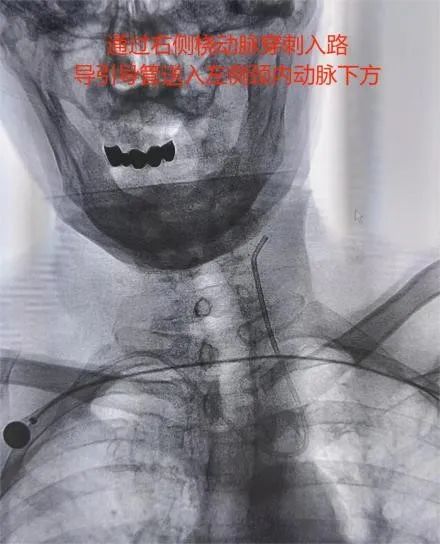

患者孙某因“急性脑梗死”来我院神经内三科就诊,完善相关检查发现该患左侧颈内动脉起始段重度狭窄。一旦闭塞将出现半身不遂等严重后果,为给予患者进一步治疗,以“颈动脉狭窄”收入我院神经内科三病区。因患者对常规股动脉穿刺入路存在恐惧心理,对导尿存在不适感,对股动脉穿刺可能产生的皮下血肿及假性动脉瘤等可能发生的并发症难以接受,经神经内三科医护团队的认真分析、研讨:1.患者右侧桡动脉搏动良好,符合穿刺置换的条件;2.Alle实验阴性;3.患者左侧颈总动脉发自头臂干,经桡动脉路径会更好到达责任血管。因此,决定由李士伟医生经右侧桡动脉入路行左侧颈动脉支架植入术。手术用时30分钟顺利完成,患者术后6小时即解除桡动脉压迫,自主 活动良好。